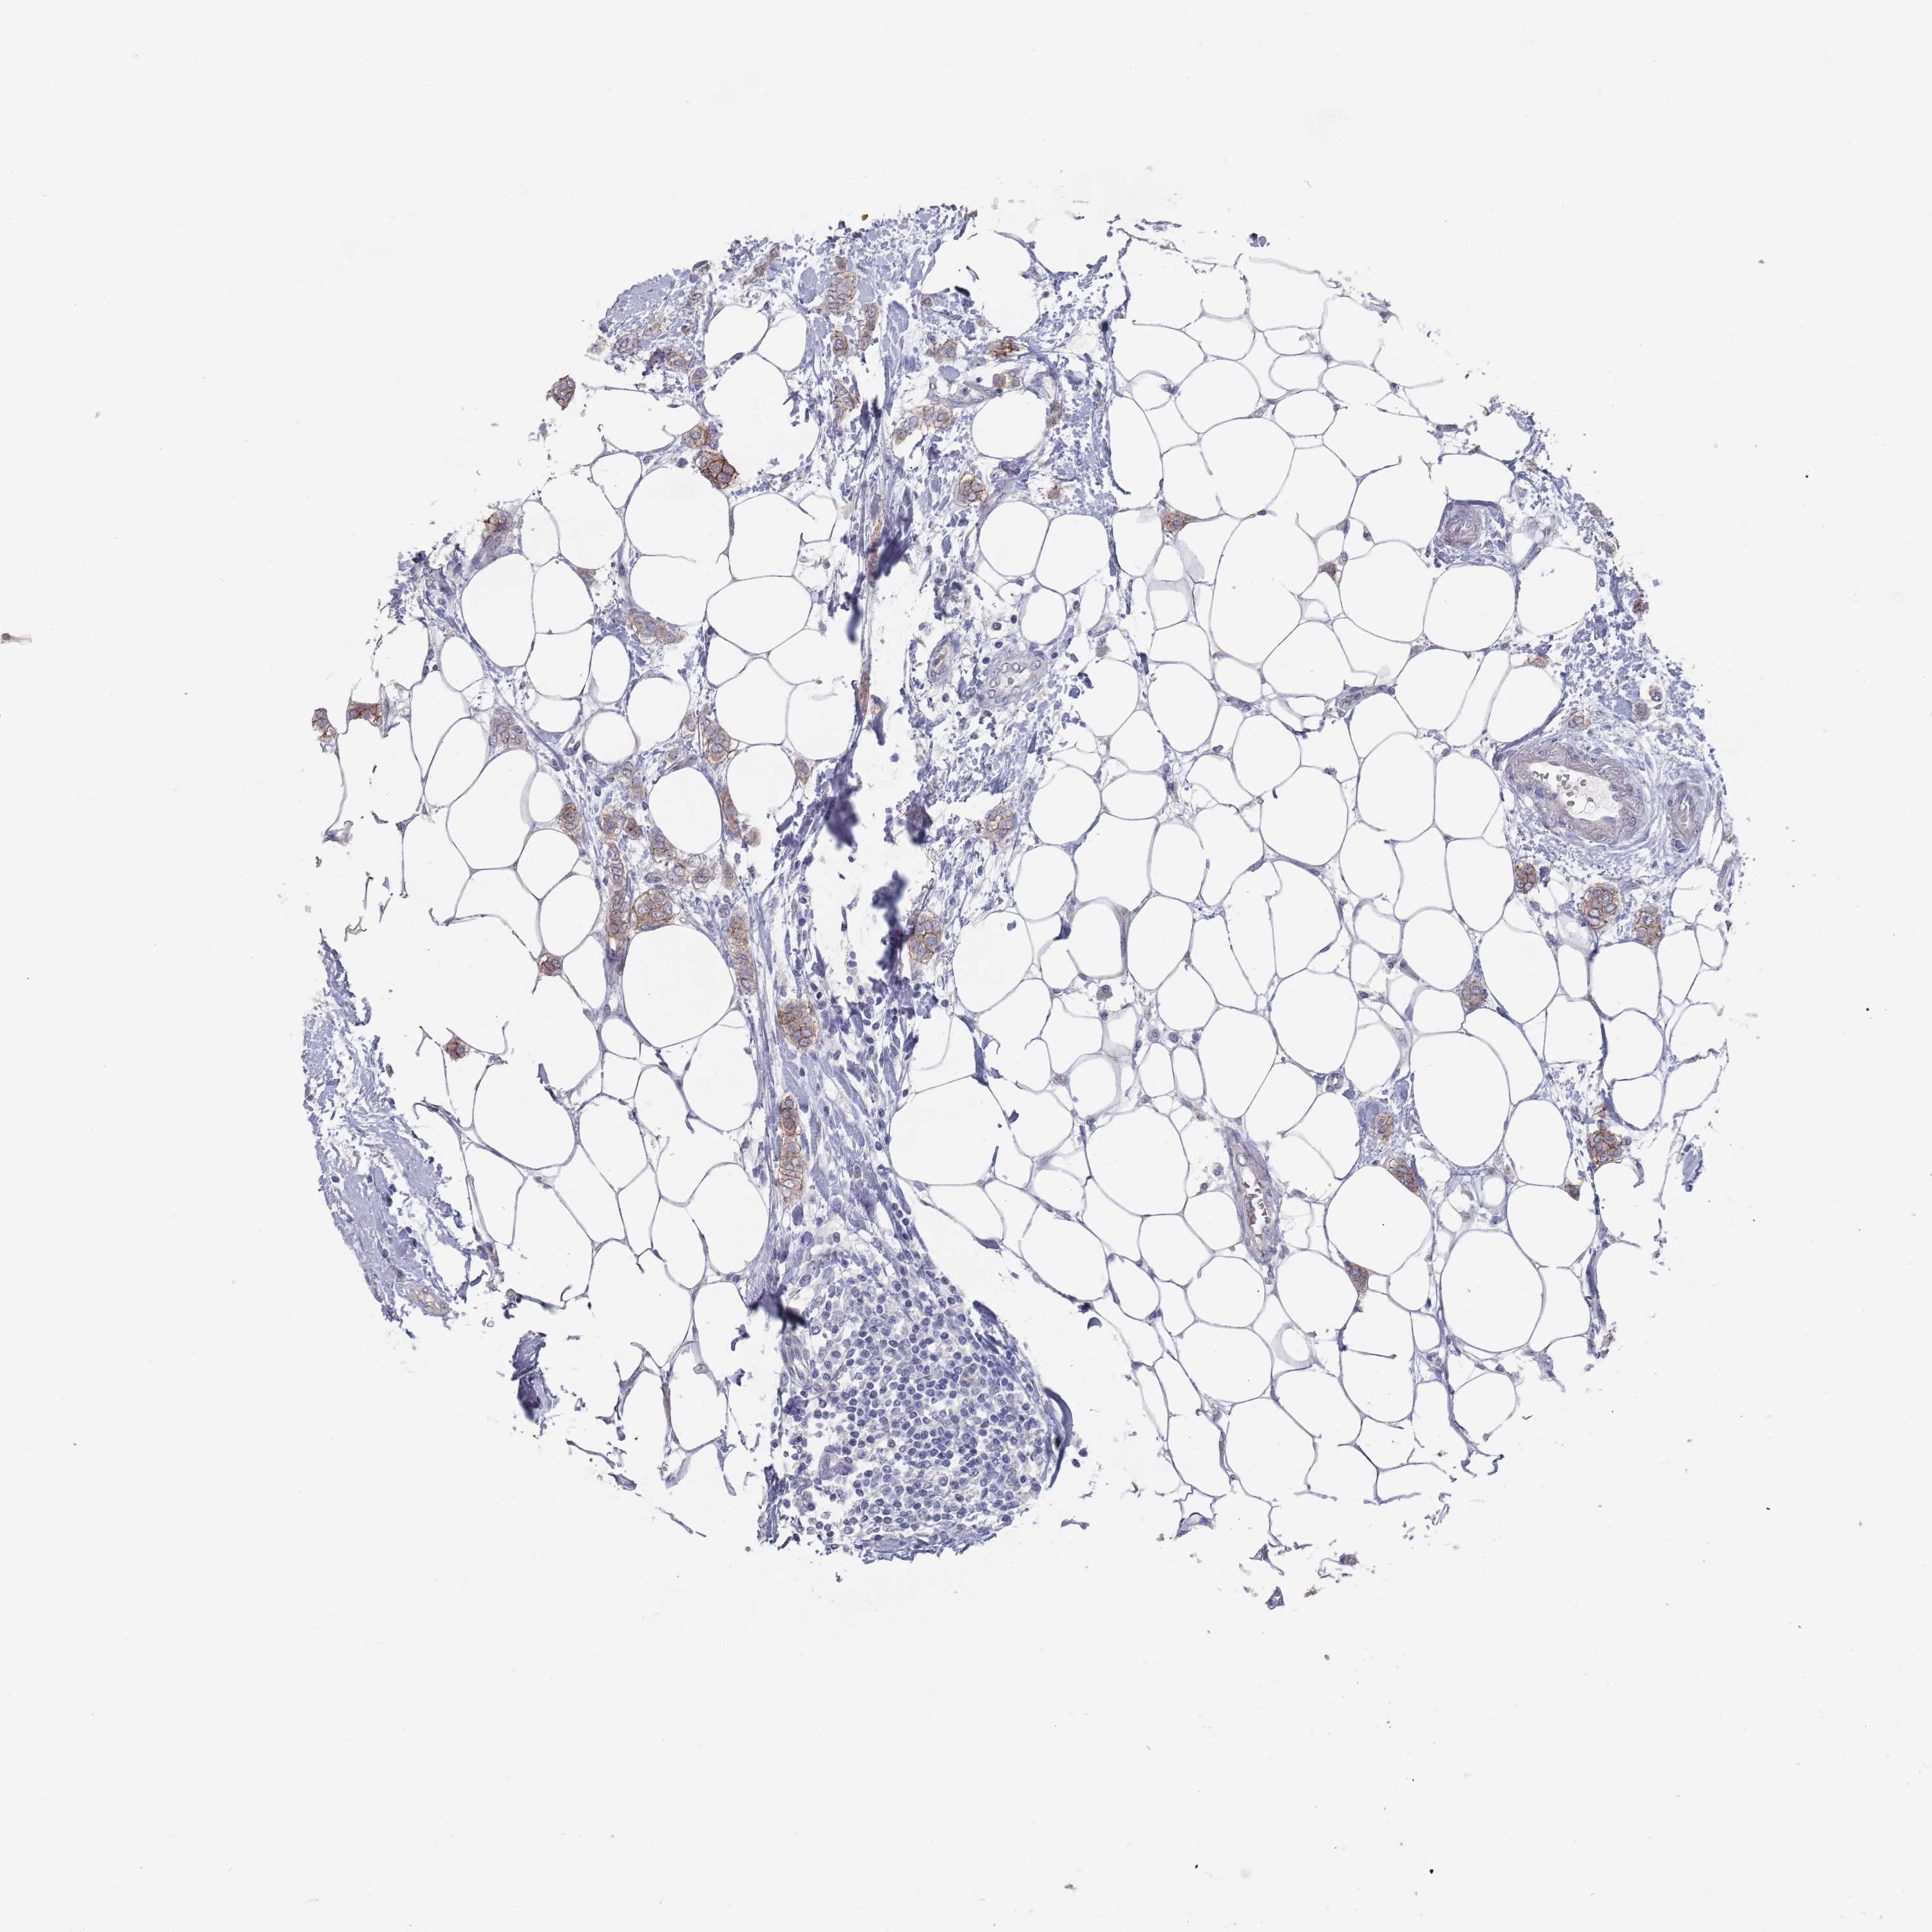

CANCER BREAST CANCER Show tissue menu

BRCA TCGA BRCA VALIDATION PROTEIN EXPRESSION